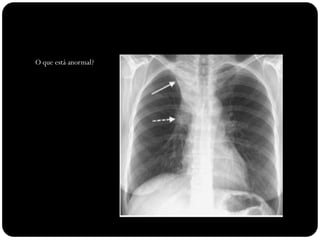

O que está anormal?

Observar:

Sinal de Luftsichel

Elevação

hemidiafrgma

esquerdo

Sinal da silhueta

(língula atelectasiada

também)